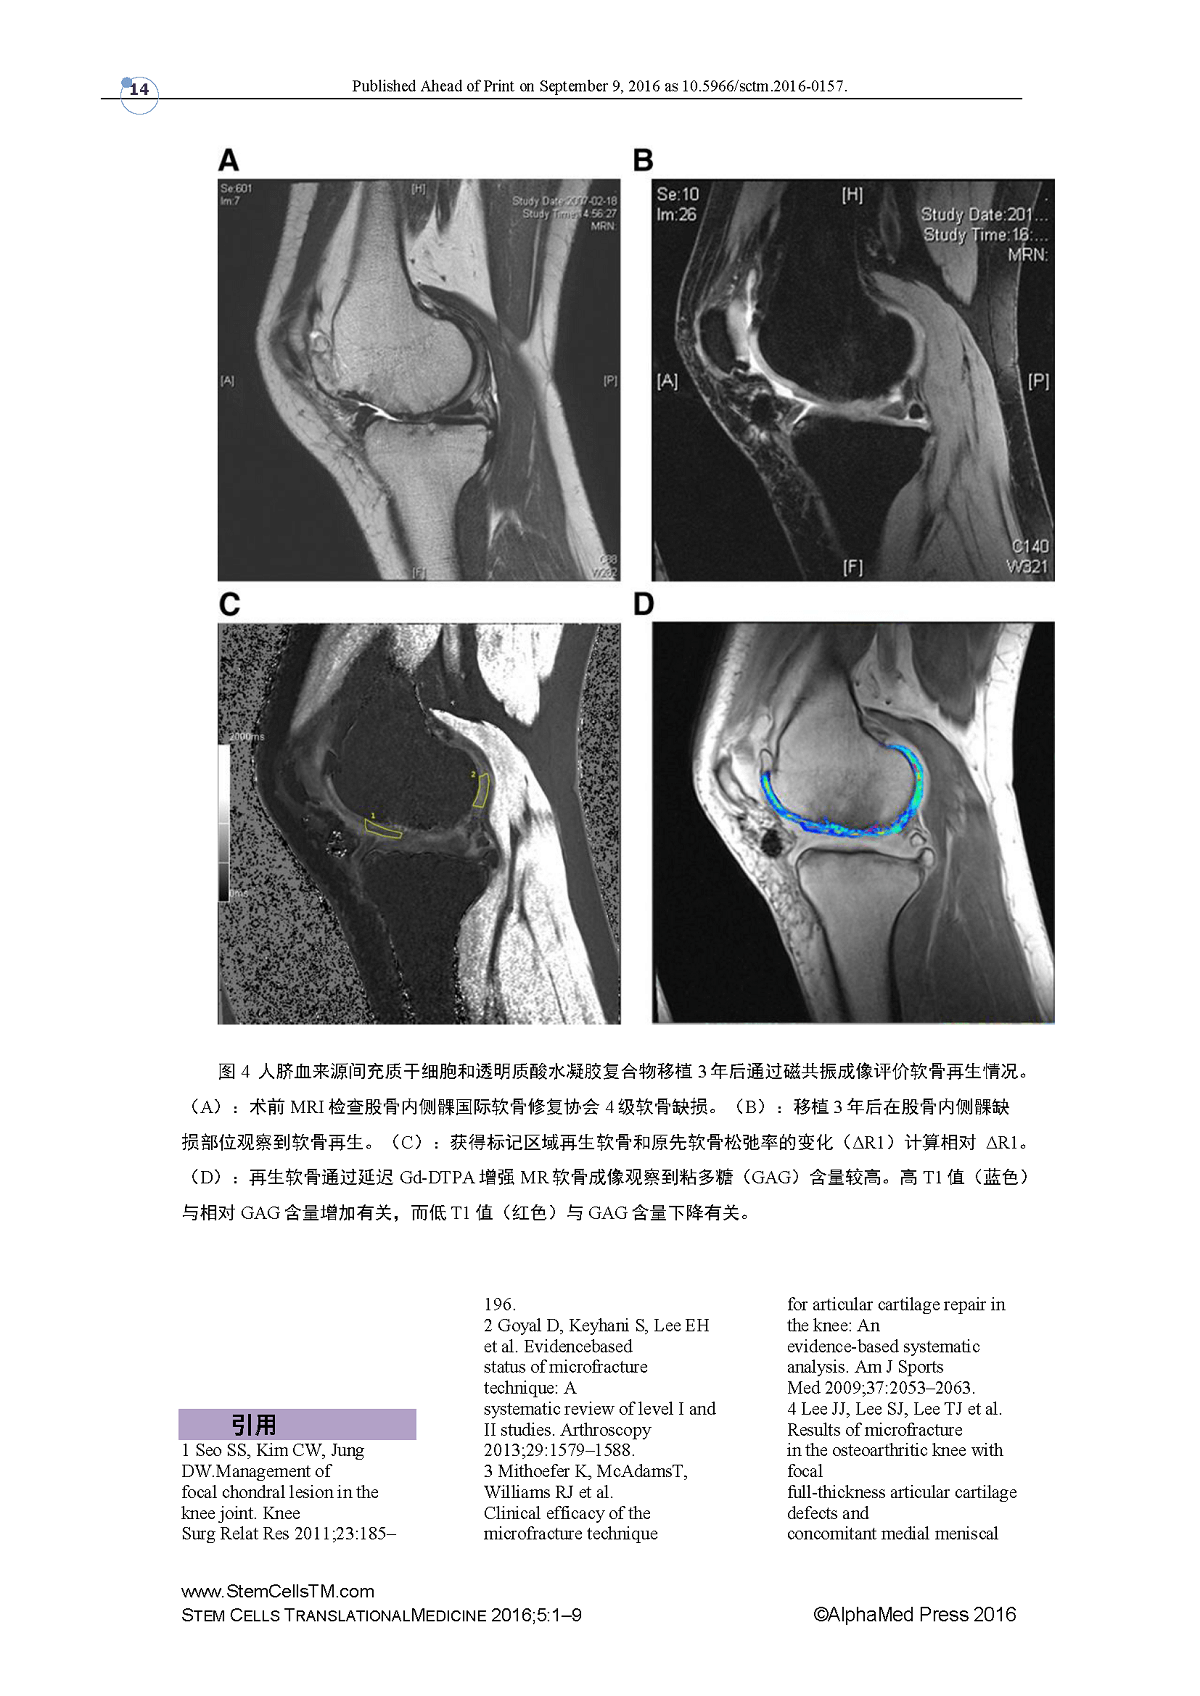

CARTISTEM七年随访结果